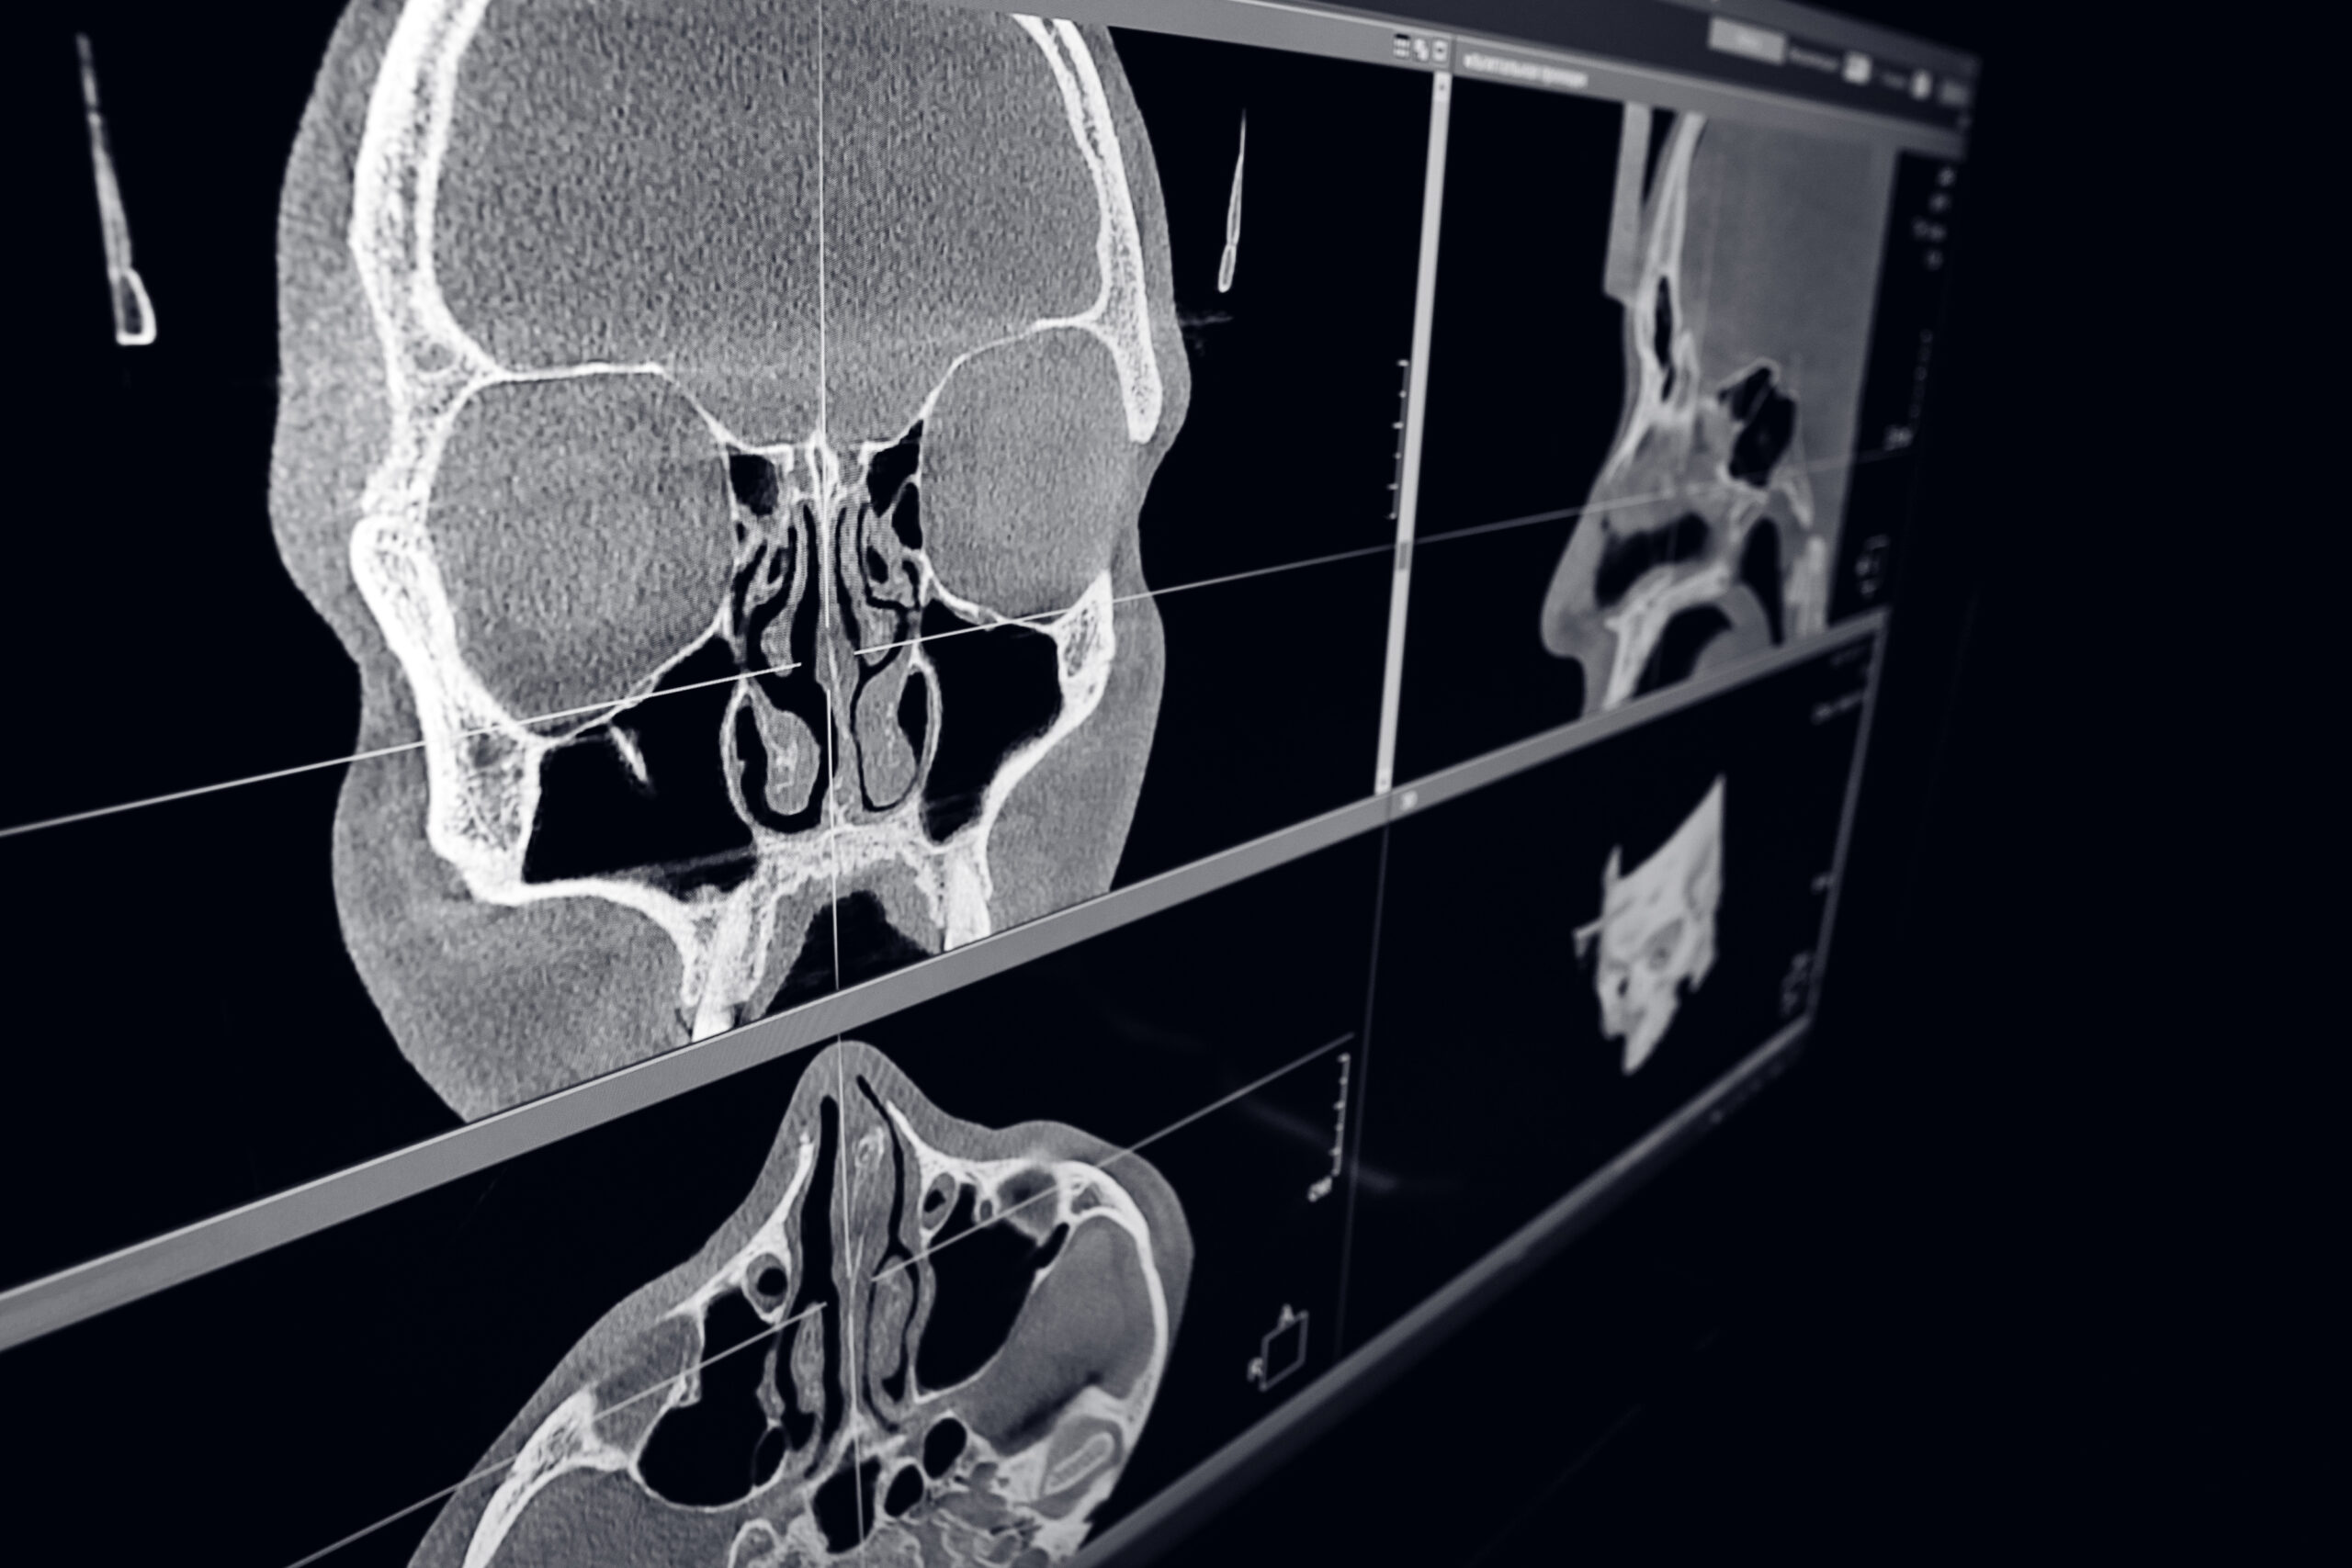

КТ ЛОР-захворювань в Харкові

Для кращої візуалізації органів «вухо-горло-ніс» та отримання найбільш достовірної інформації про їх стан у ЛОР-практиці використовується КТ з контрастуванням. ЛОР-органи мають складну фізіологічну будову, і навіть фахівцю з багаторічним досвідом роботи буває нелегко відразу поставити правильний діагноз. Завдяки високій інформативності КТ, отоларинголог має можливість отримати найповнішу інформацію про:

КТ ЛОР-органів дозволяє провести детальну оцінку стану ЛОР-органів та виявити різні патологічні процеси. Основні можливості КТ-дослідження ЛОР-органів включають:

- вивчення особливостей будови основних і додаткових пазух носа;

- виявлення деформації стінок носових ходів;

- визначення порушень функції барабанної порожнини;

- встановлення запальних процесів в області альвеолярних відростків, лобних пазух, гратчастої кістки, а також зовнішнього і внутрішнього вуха;

- виявлення абсцесів і кістозних утворень;

- визначення рівня рідини (фіброзної або гнійної);

- оцінка ступеня поширеності пухлинного процесу.

Комп'ютерна томографія ЛОР-органів забезпечує точну і своєчасну діагностику, що дозволяє лікарям приймати обґрунтовані рішення щодо подальшого лікування пацієнта.

- можливість побудови тривимірної моделі, що дозволяє виявити навіть незначні відхилення від норми;

- широкий спектр діагностичних можливостей, що включає діагностику як кісткових, так і м'яких тканин;

Під час сканування томограф робить велику кількість знімків, які необхідно обробити й переглянути лікарю-рентгенологу для отримання загальної діагностичної картини. Найбільш інформативні знімки виводяться на рентген-плівку, а весь процес сканування записується на CD-диск. Це може зайняти певний час. Висновок видається наступного дня. Інформаційний пакет КТ ЛОР-органів включає: